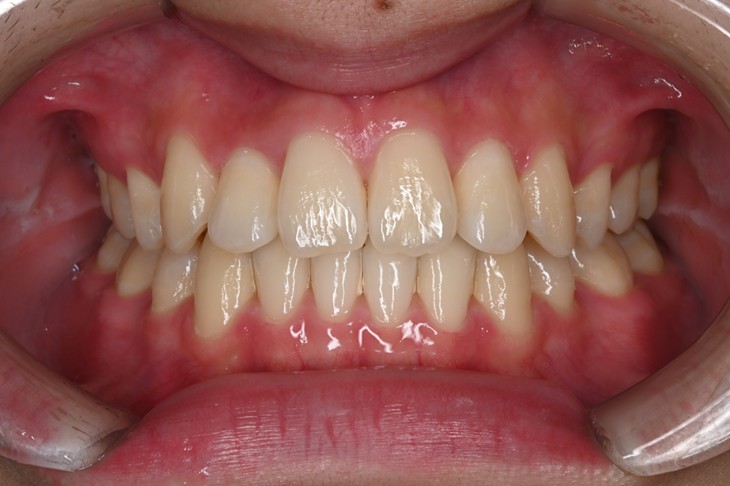

症例2:八重歯が気になる

| 患者様データ | 20代 女性 |

| 来院主訴 | 八重歯が気になる。 |

| 治療内容 | 八重歯を治すために上の親知らずを抜歯し、インビザラインにてマウスピース矯正を開始しました。かみ合わせを整えるためにゴムかけを行いました。 |

| 概算治療費 | 約85万円 |

| 治療期間 | 1年3ヶ月 |

| 通院回数 | 8回 |